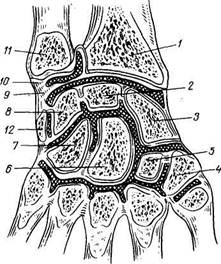

Лучезапястный сустав, art. radioedrpea (рис. 48). У большинства млекопитающих он имеет форму блока. По мере приобретения способности к пронации и супинации между лучом и локтевой костью развивается отдельный сустав — лучелоктевой дистальный, art. radioulnaris distalis,

|

Рис. 48. Фронтальный распил лучезапястного сустава (articulatio radiocarpea) и суставов кисти.

/-radius; 2 - os lunatum; 3 - os scaphoideum; 4- os trapezium; 5 — os trapezoideum; 6 — os capitatum; 7 — os hamatum; 8 — os triquetrum; 9 — discus articu-laris, 10 — lig. collaterale carpi ulnare; 11 — ulna; 12 — os pisiforme.

который вместе с проксимальным лу-челоктевым суставом образует единое комбинированное сочленение с вертикальной осью вращения. В этом комбинированном сочленении лучевая кость движется вокруг локтевой, вследствие чего значительно увеличивается ди-стальный эпифиз луча. Наоборот, ди-стальный эпифиз локтевой кости отстает в своем развитии и становится короче луча, но зато на нем возникает специальный суставной диск, discus arti-cularis. У человека в связи с наибольшим объемом супинации и пронации

discus articularis достигает наивысшего развития и приобретает форму треугольной волокнисто-хрящевой пластинки, fibrocartilago triangulare, которая срастается с дистальным эпифизом лучевой кости и вместе с ним образует суставную впадину проксимального отдела лучезапястного сустава. Следовательно, локтевая кость участвует в лучезапястном суставе лишь посредством названного хрящевого диска, не имея к этому сочленению непосредственного отношения, поэтому проксимальный отдел этого сустава называется не предплечезапястным суставом, а лучезапястным.

В соответствии с указанным выше суставная впадина art. radiocarpea образована fades articularis carpea луча и discus triangularis, a суставная головка этого сустава — проксимальной поверхностью первого ряда костей запястья, os scaphoideum, lunatum et triquetrum, которые связаны между собой межкостными связками, ligg. intercarpea. По числу участвующих костей сустав является сложным, а по форме суставных поверхностей относится к эллипсовидным с двумя осями вращения (сагиттальной и фронтальной).

Соединение костей кисти, articulationes manus. 1. Среднезапястное сочленение, art. mediocarpea, находится между первым и вторым рядом костей запястья, за вычетом гороховидной кости, являющейся сесамовидной. Суставной впадиной этого сустава служит дистальная поверхность первого ряда костей запястья. Проксимальная поверхность второго ряда запястья образует суставную головку.

Оба кистевых сустава (лучезапястный и среднезапястный) имеют самостоятельные суставные капсулы, прикрепляющиеся по краям их суставных поверхностей. Укреплению капсулы лучезапястного сустава служат с лучевой и локтевой сторон вспомогательные связки: lig. collaterale carpi radiate, идущая от шиловидного отростка луча к ладьевидной кости, и lig. collaterale carpi ulnare, протягивающаяся от шиловидного отростка локтевой кости к os triquetrum и os pisiforme. На ладонной стороне лучезапястного сустава находится lig. radiocarpeum palmare, которая, начавшись широко от шиловидного отростка и от края суставной поверхности луча, несколькими пучками прикрепляется к os scaphoideum, lunatum, triquetrum et capitatum. С тыльной стороны капсула лучезапястного сустава под-

крепляется lig. radiocarpeum dorsale, которая идет от луча к костям первого ряда костей запястья. У места прикрепления связок лучезапястного сустава к костям в последние входят кровеносные сосуды и нервы, повреждение которых при операциях влечет за собой патологические изменения в костях. Капсула art. mediocarpea захватывает и четыре последних запястно-пястных сустава, сообщающихся между собой. Кроме art. mediocarpea, отдельные кости запястья, соединенные друг с другом межкостными связками, ligg. intercarpea interossea, местами сочленяются между собой обращенными друг к другу сочленовными поверхностями. Такие суставы называются межзапястными, articulationes intercarpeae.

Межзапястные сочленения подкрепляются рядом коротких связок, идущих большей частью поперечно от одной кости к другой на тыльной, ligg. intercarpea dorsalia, и ладонной, ligg. intercarpea palmaria, сторонах. На ладонной стороне, кроме того, отмечают пучки, расходящиеся от головчатой кости к соседним костям, lig. carpi radiatum. Движения в кистевых суставах совершаются вокруг двух взаимно перпендикулярных осей, проходящих через головку головчатой кости, вокруг фронтальной (сгибание и разгибание) и вокруг сагиттальной (отведение и приведение). Эти движения тормозятся связками, которые расположены перпендикулярно осям вращения и по концам их, а именно: коллатеральные — по концам фронтальной оси, тыльные и ладонные — по концам сагиттальной. Поэтому первые тормозят отведение и приведение вокруг сагиттальной оси, а вторые — сгибание и разгибание вокруг фронтальной. Как во всех двухосных суставах, здесь возможно и circumductio, при котором концы пальцев описывают круг.

На ладонном рентгеновском снимке кисти видны все участвующие в ее образовании кости и их детали (рис. 50). «Рентгеновские суставные щели» имеют вид полос просветлений между суставными поверхностями соответствующих костей.

«Рентгеновская щель» лучезапястного сустава в медиальной части расширена соответственно расположенному здесь суставному диску (треугольному хрящу), не задерживающему рентгеновских лучей.